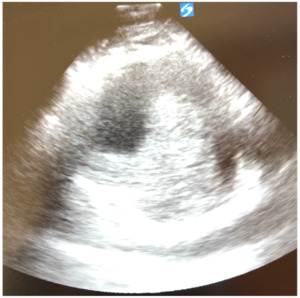

However, upon further careful medical history taking, the patient also reported chest pain that started that morning. He stated that the pain was located over the left side of his chest, felt sharp, was intermittent, but not worsened with exertion. He denied any recent upper respiratory infection, trauma to the chest, history of drug use, or previous history of chest pain.6 Although his blood pressure and heart rate were mildly elevated, his cardiac examination was normal, and he had good pulses in all of his extremities. We ordered tests to assess for potential acute coronary syndrome including electrocardiograms (ECG), high sensitivity troponins, and chest radiography. The ECG (Figure 2) showed sinus tachycardia at about 102 beats per minute, poor R wave progression across the precordial leads suggestive in this case of previous anteroseptal injury, and left ventricular hypertrophy per the modified Cornell criteria, but no ST segment elevations concerning for acute cardiac ischemia. The high-sensitivity troponin was very minimally elevated to 0.07 and downtrended to 0.06 three hours later. All other labs were grossly unremarkable besides mildly elevated liver function tests. The portable chest radiograph, however, showed a modestly widened superior mediastinum, as pictured in Figure 3. We quickly proceeded with a bedside ultrasound which showed a large ascending aortic aneurysm (Figure 4) with an associated proximal aortic dissection. In Figure 5, a dissection flap can be clearly visualized. After consulting with cardiothoracic surgery while starting the patient on an esmolol drip for blood pressure and impulse control, we obtained a CT angiogram of the chest which showed a 7.7 cm dissecting aneurysm involving the ascending aorta and proximal aortic arch with a large, partially thrombosed false lumen and extension into the proximal innominate artery (Figure 6). The radiologist also noted there was marked compression of the superior vena cava (SVC) due to the large aneurysm of the ascending aorta. The patient later required a nicardipine drip after high-dose esmolol failed to optimally control his hyperdynamic state.